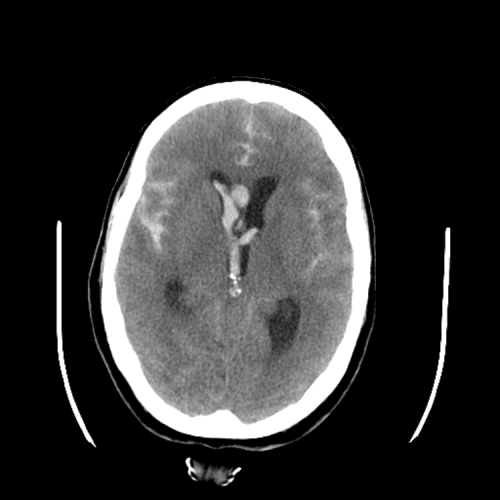

Cardioembolic infarcts